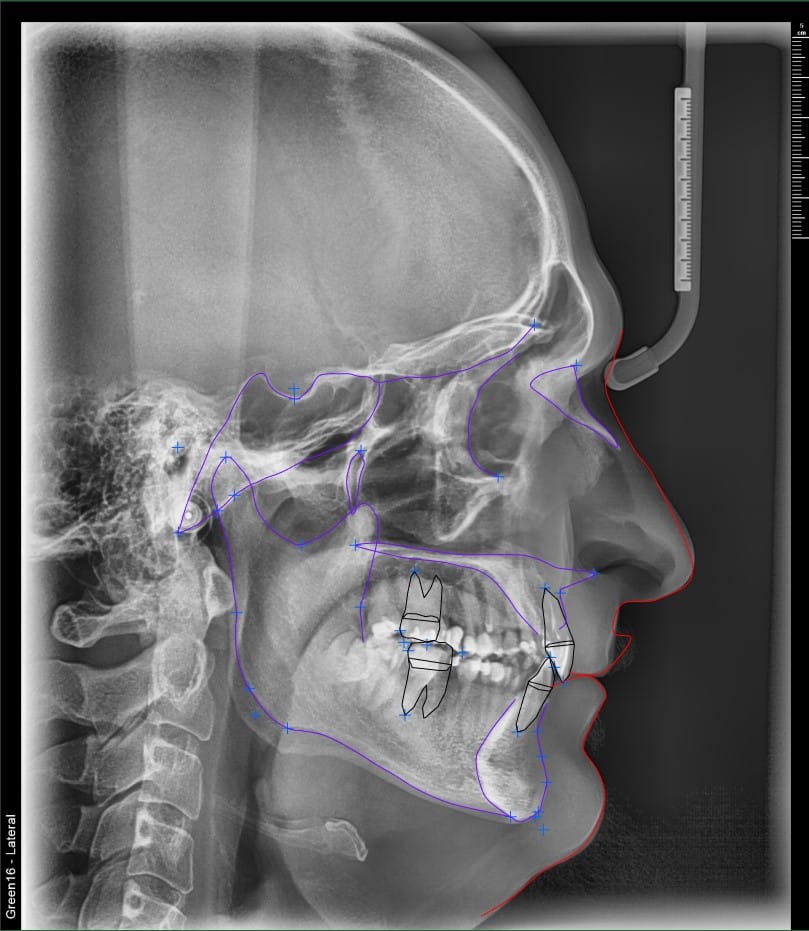

Efectuăm teleradiografii de profil cu analiză completă la solicitarea medicului specialist ortodont. Vă oferim lista completă de măsurători ortodontice pe care le putem efectua: McLaughlin, Steiner, Tweed, Ricketts, Method II, Method I, McNamara, Jarabak.